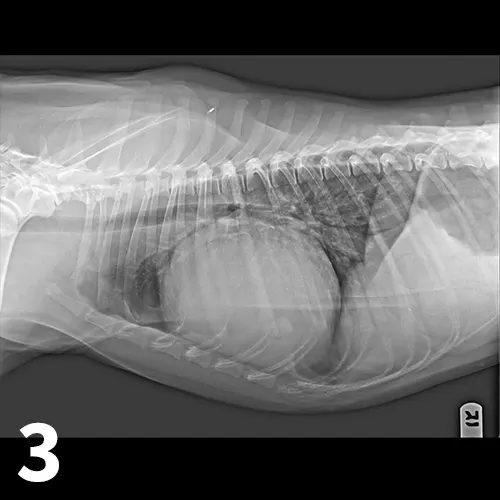

Figure 3

Right lateral thoracic radiograph for patient presenting with acute collapse. The heart is globoid while the pulmonary vasculature is small. The caudal vena cava is hard to visualize but would likely be dilated.

• The heart may be relatively normal (acute hemorrhage) or globoid (chronic effusion; Figure 3). Distention of the caudal vena cava, ± pleural effusion, ± peritoneal effusion, may also be present.